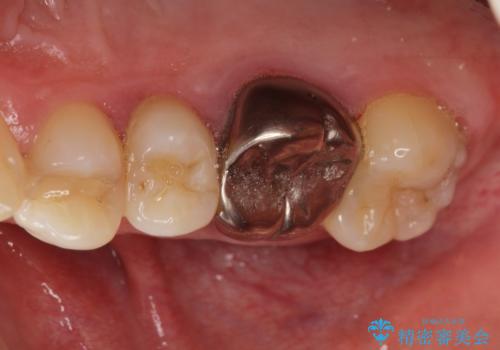

歯頚ラインが変えられないことや天然歯を削るリスクをご理解頂いた上で、オールセラミッククラウンによる補綴治療を行いました。(見えない奥歯のみ天然歯のままとしました)

下の前歯1本だけ歯軸を変えるために神経をとり根管治療を行っております。

それ以外の歯は神経をとらずに済むよう、慎重かつ丁寧に歯の形態を整えました。